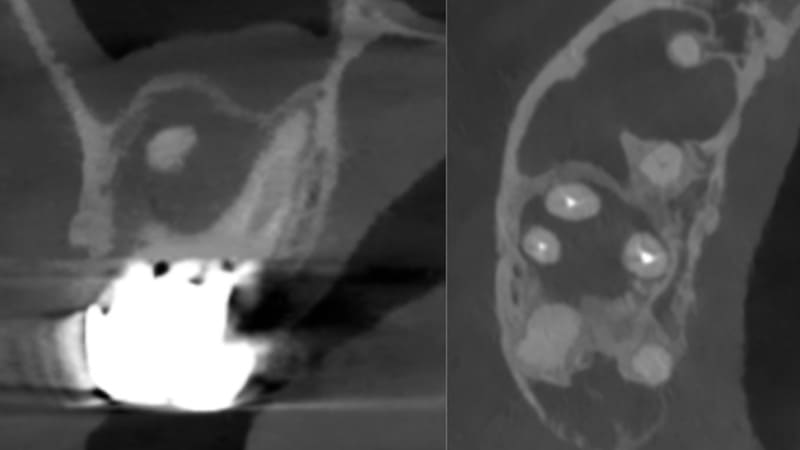

症例②:右上の奥歯がたまにうずく

| 治療科目 | 根管治療、セラミッククラウン |

|---|---|

| 主訴 | 右上の奥歯がたまにうずく |

| 治療期間 | 3ヶ月 |

| 治療費 | セラミッククラウン 121,000円 |

| 治療内容 | 奥歯、銀歯を除去しマイクロスコープを使い根管内洗浄、根管充填した。仮歯で1ヶ月経過観察後症状消失したため最終補綴(ジルコニアクラウン)装着。 |

| 治療のリスク | 噛み合わせが強い場合歯根破折の可能性あります。 まれに再発する可能性があります。 その場合外科的歯内治療をするか、抜歯を検討します。 |